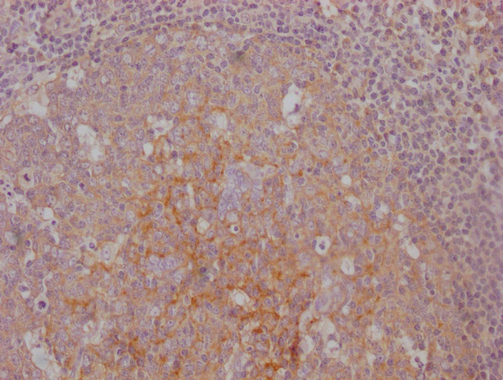

• IHC image of CSB-MA792948 diluted at 1:100 and staining in paraffin-embedded human tonsil tissue performed on a Leica BondTM system. After dewaxing and hydration, antigen retrieval was mediated by high pressure in a citrate buffer (pH 6.0). Section was blocked with 10% normal goat serum 30min at RT. Then primary antibody (1% BSA) was incubated at 4°C overnight. The primary is detected by a Goat anti-mouse IgG polymer labeled by HRP and visualized using 0.05% DAB.